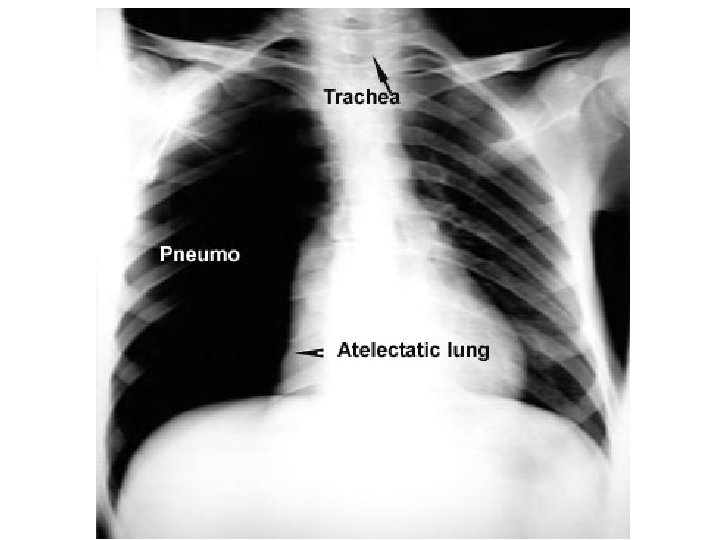

Air in pleura Atelectatic lung Hemithorax Mediastinual shift Pneumothorax